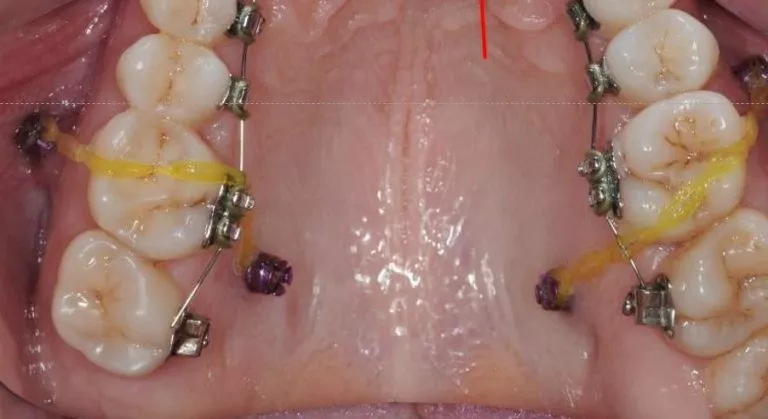

שתלים אורתודונטים

שתלים אורתודונטים הינם ברגים עדינים, המוחדרים ללסת ומסייעים לביצוע הטיפול כמקור להפעלת כוחות.

שיטה זו הינה חדשנית ומתקדמת ביותר ויעילה מאוד במקרים בהם חסרות שיניים או קיימת מגבלה להפעלת כוחות על שיניים כמו במחלות חניכיים.